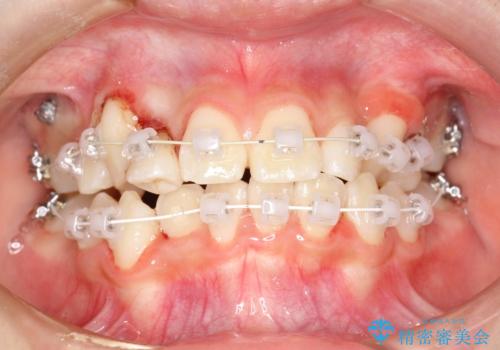

- 審美装置、リンガルアーチ

過剰歯と乳歯を抜歯後、リンガルアーチを用いて大まかな移動を行った後、マルチブラケットへ移行し、可及的に正常咬合へと誘導することを試みた。

乳歯・過剰歯を除去し、リンガルアーチを用いて埋伏していた犬歯を牽引、その他おおまかな動きを行った後、マルチブラケットにて永久歯の咬合を誘導しました。